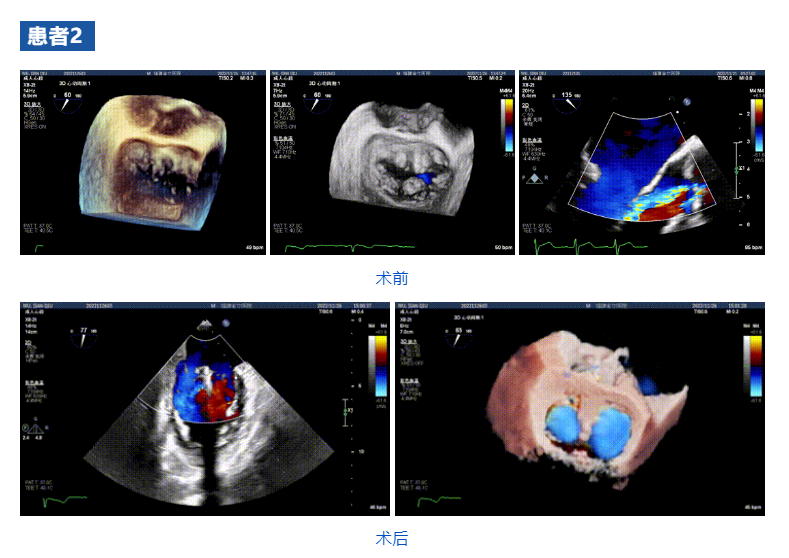

接受治療的三例患者均為器質(zhì)性重度二尖瓣反流(DMR)患者,術(shù)前超聲提示二尖瓣后葉脫垂伴4+反流,左室舒張功能減退。郭延松教授攜同團(tuán)隊成員陳新敬副教授和洪景宣、方明程、楊清勇主治醫(yī)師、心外科丁杭主任以及超聲科賴寶春、葉振盛主治醫(yī)師共同進(jìn)行病情討論。考慮到患者高齡、基礎(chǔ)疾病多、STS評分高,為外科手術(shù)極高危患者,不適合進(jìn)行外科開胸二尖瓣手術(shù),因此決定為患者實施經(jīng)導(dǎo)管緣對緣修復(fù)介入術(shù)(JensClip經(jīng)導(dǎo)管瓣膜夾系統(tǒng))。

在浙江大學(xué)醫(yī)學(xué)院附屬第二醫(yī)院王建安教授團(tuán)隊的支持下,手術(shù)經(jīng)股靜脈-房間隔入路,采用全身麻醉插管,在TEE和DSA引導(dǎo)下完成房間隔穿刺。置入JensClip瓣膜夾系統(tǒng)后,在左房調(diào)整瓣膜夾的位置和軸向,后進(jìn)入左室,在TEE引導(dǎo)下捕捉二尖瓣前后瓣葉,并關(guān)閉瓣膜夾。經(jīng)TEE反復(fù)確認(rèn)手術(shù)效果后最終鎖定并釋放瓣膜夾。術(shù)后即刻超聲顯示瓣膜夾位置穩(wěn)定,功能良好,二尖瓣反流由術(shù)前4+減少至微量,手術(shù)圓滿成功。